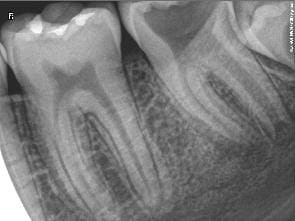

Je vous demande conseil pour la dent 37 que vous pouvez voir ci joint.

Le patient se présente avec une douleur non rémanente, non pulsatile. Je sonde et trouve un point de carie ressemblant à un point de carie arretée, mais je m'enfonce allègrement avec la sonde, je prend la radio (voir "sans titre"), je vois cette carie "surprise" :)

Radio faite : voir "Sans titre 2"

Je ne trouve rien de changer...pour la racine mésiale en tout cas, mais apres avoir tenté de prendre l'apex distal 4 fois et quil est failli me vomir dessus a chaque reprise, j'ai abandonné...